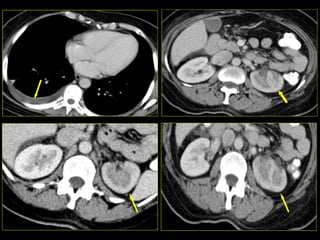

Caso # 7 ♀ , 45 años,  dolor abdominal difuso, sin poder determinarse la causa clínicamente por lo que se envía a TC para búsqueda de la probable causa de dolor. Estudio en fases arterial, venosa y excretora, mostrándose cortes axiales.

FASE ARTERIAL

FASE VENOSA

Hallazgos Caso # 7: Hay un área triangular de disminución de la atenuación en la parte posterolateral del  riñón izquierdo, las cuales se demuestran en fases contrastadas, y en fase excretora muestran persistencia del medio de contraste, en relación con proceso inflamatorio focal.